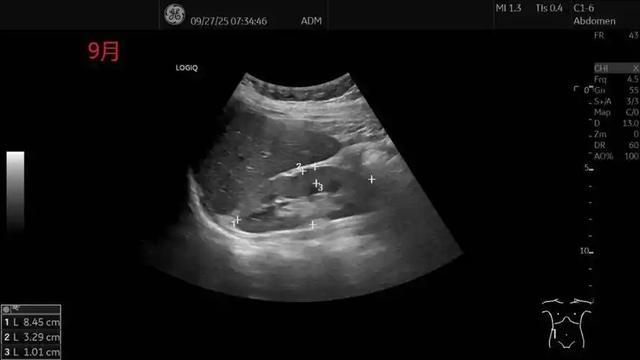

面对异常结果,不必恐慌,但也不能漠视。正确的做法是携带完整报告,前往肾内科或泌尿外科就诊。医生可能会建议做尿蛋白定量、肾功能血液检查(如肌酐、尿素氮)、甚至肾脏超声等进一步检查。早发现、早干预,很多肾脏疾病是可以被有效控制的。